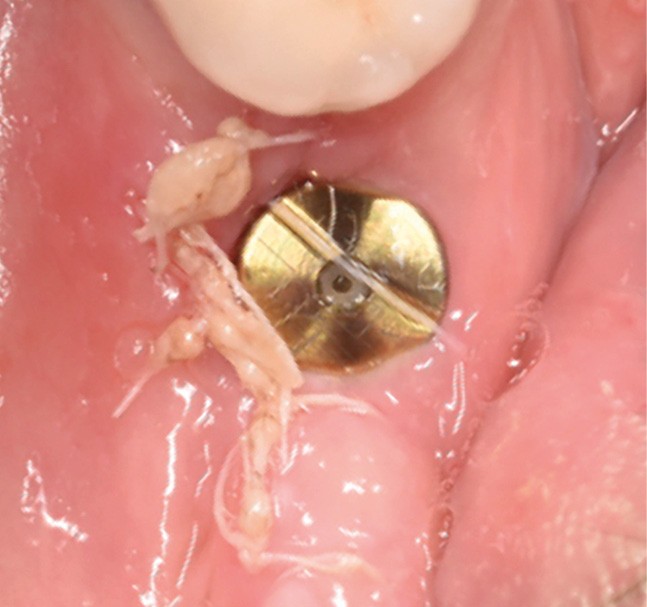

Actes préopératoires

La couronne a été déposée et une vis de couverture mise en place. La patiente a reçu un nettoyage supra-gingival général avec une attention particulière pour l’implant 47, et une irrigation locale avec du gel de chlorhexidine et du peroxyde d’hydrogène pour réduire l’inflammation des tissus. De l’amoxicilline (3 x 500 mg) a été prescrite, à commencer la veille de l’intervention chirurgicale.